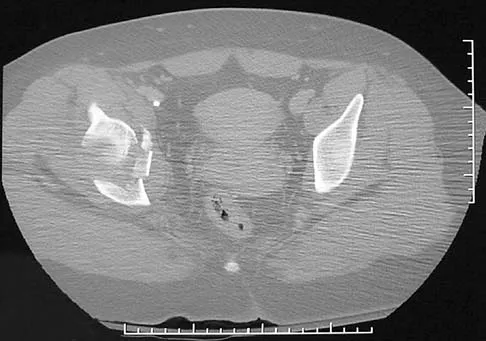

Figures 61a and 61b show the CT and MRI scans of a 40-year-old man who has hip pain. He undergoes total hip arthroplasty and curettage and cementation of the lesion as shown in Figure 61c. Histopathologic photomicrographs of the curettage specimen are shown in Figures 61d and 61e. What is the best course of treatment?

Explanation

The definitive surgery would be removal of the entire resection bed, and in this case of dedifferentiated chondrosarcoma, a hemipelvectomy was performed. The MRI and CT scans show an aggressive cartilage lesion. The histology, representative of a dedifferentiated chondrosarcoma, shows a bimorphic low-grade cartilage lesion with high-grade spindle cell sarcoma. The cartilage lesion is usually an enchondroma or low-grade chondrosarcoma. The dedifferentiated portion is typically a malignant fibrous histocytoma, osteosarcoma, or fibrosarcoma. Weber KL, Pring ME, Sim FH: Treatment and outcome of recurrent pelvic chondrosarcoma. Clin Orthop Relat Res 2002;397:19-28.